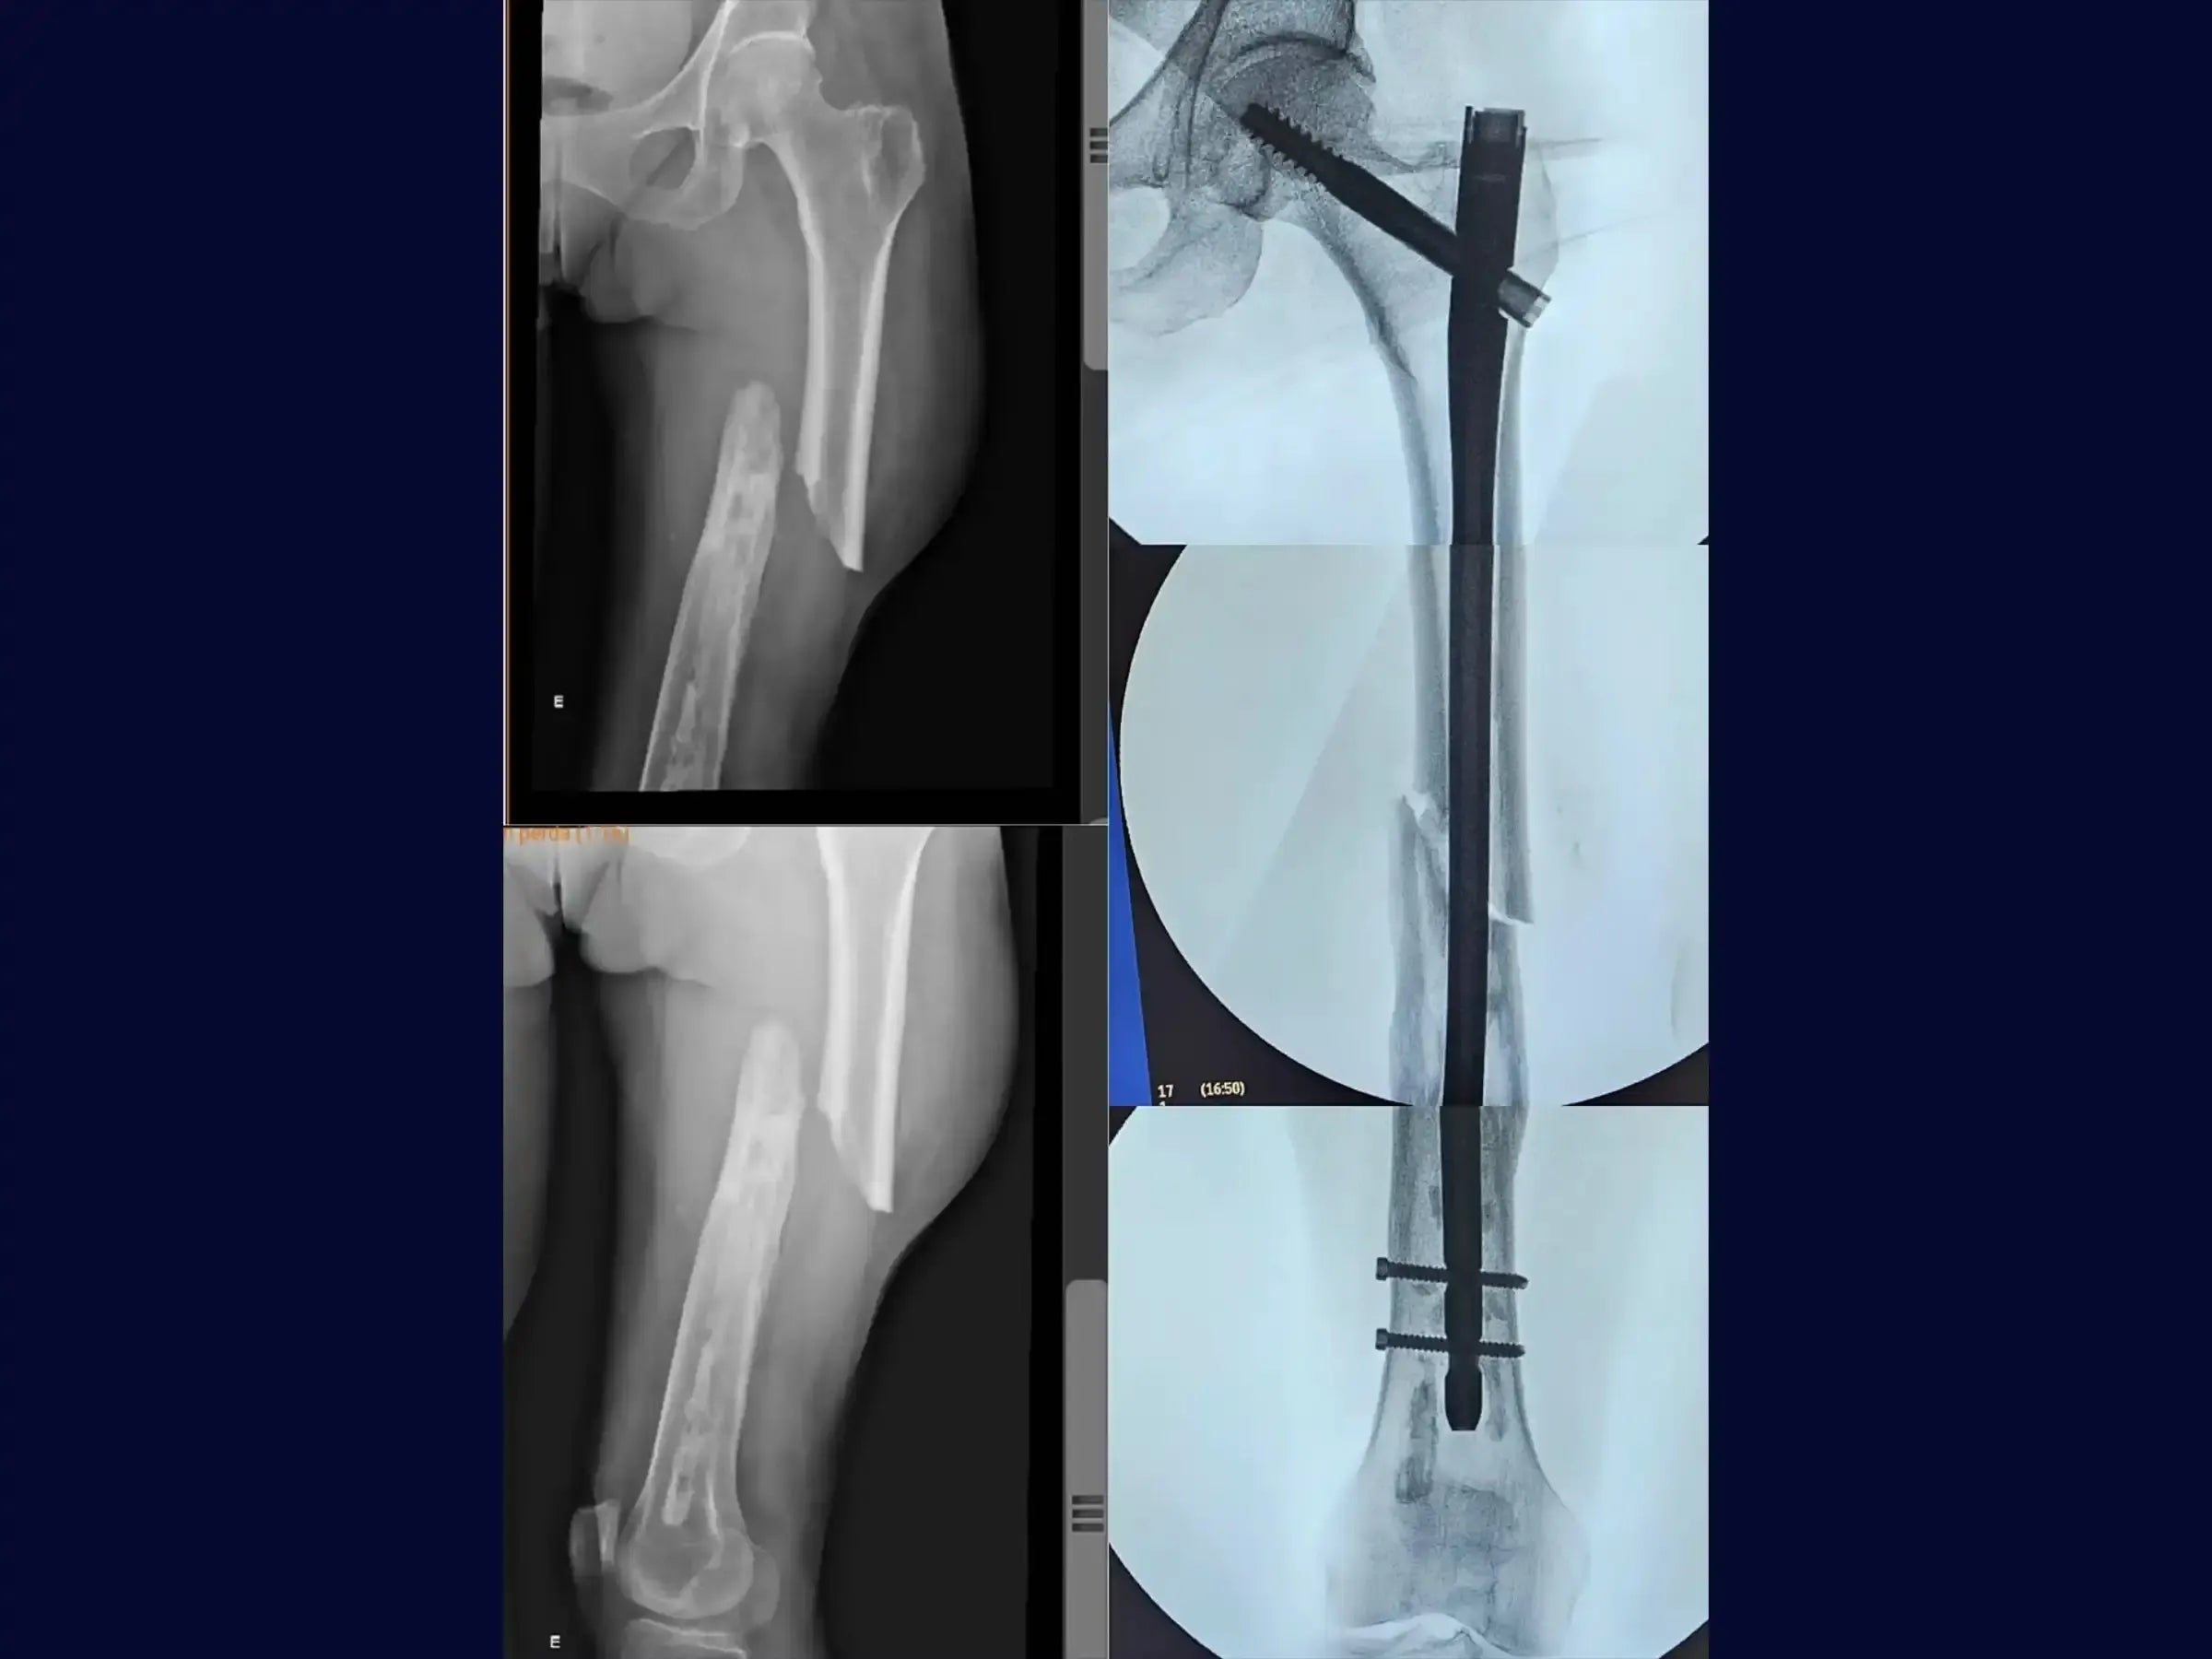

Domine o tratamento de refraturas diafisárias do fêmur, especialmente em casos de fragilidade óssea local, com foco na reabilitação precoce. Este treinamento oferece uma imersão técnica na osteossíntese com haste intramedular anterógrada cefalomedular, enfatizando uma abordagem minimamente invasiva sem o uso de mesa de tração.

- Tratamento de refraturas diafisárias do fêmur, inclusive em pacientes com fragilidade óssea.

- Técnica de fixação com haste intramedular anterógrada cefalomedular.

- Fixação Proximal com Haste Cefalomedular: Utilize uma haste cefalomedular de 11 milímetros de diâmetro e confeccione um acesso lateral para a fixação do parafuso deslizante. Realize a medição e posicionamento sincronizado do parafuso deslizante, buscando o centro da cabeça do fêmur nas projeções AP e perfil, mesmo em fraturas diafisárias.

- Bloqueio Distal de Alta Precisão: Domine a técnica de bloqueio distal utilizando um miniportal de pele alinhado com o túnel ósseo para evitar dificuldades com partes moles. Aprenda a alinhar a broca com o intensificador de imagem, utilizando a primeira broca como guia para a segunda, garantindo paralelismo e evitando a perda do furo devido a manipulações do membro inferior. Compreenda a importância da precisão na primeira perfuração para a agilidade do bloqueio e para evitar a inserção inadvertida do parafuso em um orifício incorreto.